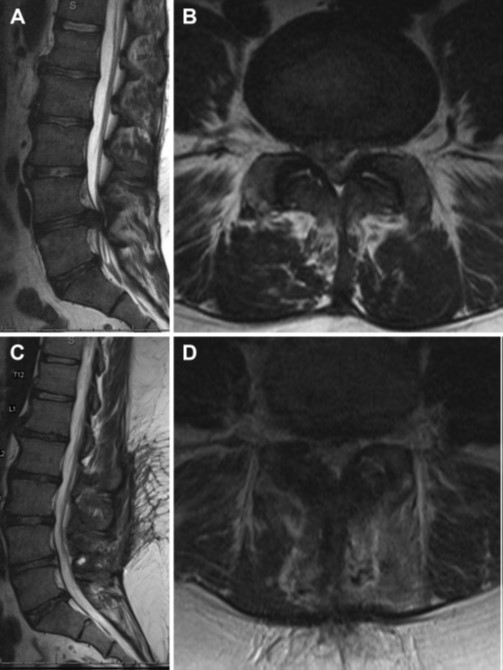

Hình 2. MRI cột sống thắt lưng không và có tiêm Gadolinium cho thấy hình ảnh viêm xương tủy xương ở L1 và L2. Mô nhiễm khuẩn đồng tín hiệu trên T1 (A), tăng nhẹ tín hiệu trên T2 (B) và bắt tương phản sau tiêm Gado (C).

Bn nam, 25 tuổi, đến khám trong bối cảnh xuất hiện đau lưng cấp tính nặng lên trên nền đau lưng mạn tính, đồng thời có dị cảm ở háng và chân phải, đau ở chân bên phải dọc theo vùng do rễ L4 chi phối, giảm nhu động ruột và bàng quang ứ đọng nước tiểu sau tiểu tiện (incomplete voiding). Khám cho thấy sức cơ động tác gập cổ chân (dorsiflexion) và duỗi cổ chân (plantar flexion) là 4/5 ở hai bên, thay đổi cảm giác ở vùng đáy chậu, nhưng trương lực cơ trực tràng bình thường. Huyết áp là 121/70, áp lực động mạch trung bình là 87, nhịp tim 64/phút, Sa O2 là 94%. BN được chụp MRI và có hình ảnh như sau (hình 14)

Hình 14. Lát cắt dọc qua đường giữa (A) và ngang (B) trên chuỗi xung T2 ở vùng cột sống thắt lưng cho thấy thoát vị đĩa đệm cạnh trung tâm ở L4/L5 gây chèn ép chùm đuôi ngựa. Hình ảnh cắt dọc qua đường giữa (C) và ngang (D) trên chuỗi xung T2 sau mổ lấy khối thoát vị cho thấy chùm đuôi ngựa được giải ép rõ.